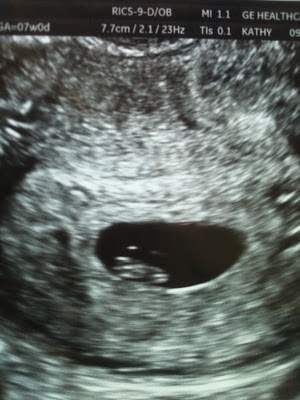

We had our 11 week ultra sound today and I have to say it is by far the neatest experience I've had in my entire life. The water works were in full motion! I went in for one at 7 weeks and it was neat, but that was for an emergency and I was so busy being relieved that my little blob in there was ok that I didn't experience the sense of wonder that this one was. I don't think anything could have prepared me for it. To see our little baby in there moving around, stretching out those arms and legs and that tiny little face.....there just aren't words. Of course all of you mom's know exactly what I'm talking about, its so amazing. I find myself anxious to go back in 4 weeks to check on my little baby bean again. This past month and a half of suffering suddenly feels entirely worth it. I can't believe how much my attachment has grown from this experience alone.

7 Weeks

11 Weeks 3 Days